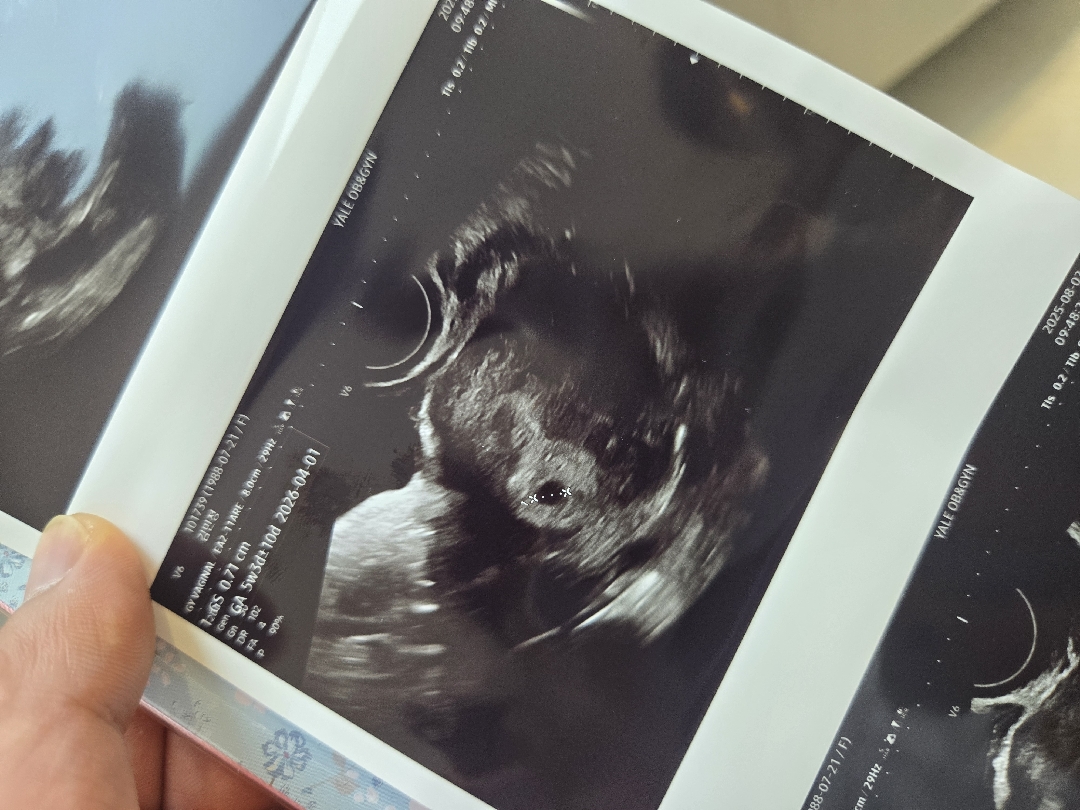

저번주 토요일에 아기집봤어용 ! 일주일뒤인 이번주 토요일에 난황보러 오라는데 볼수있겠죠? 딱 5주차에 아기집 0.71cm 였는데 주수에 비해 아기집이 크다고 했거든요 ! 빨리 난황보고 심소듣구싶네요 ㅠㅠ